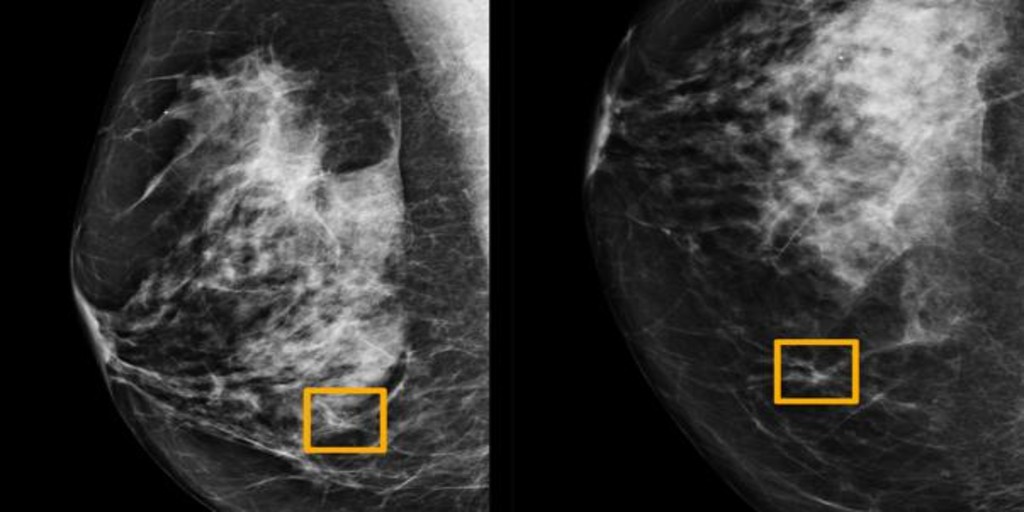

El diagnóstico precoz es la mejor estrategia contra el cáncer de mama. A partir de los 40 años todas las mujeres deben realizar una mamografía anual.